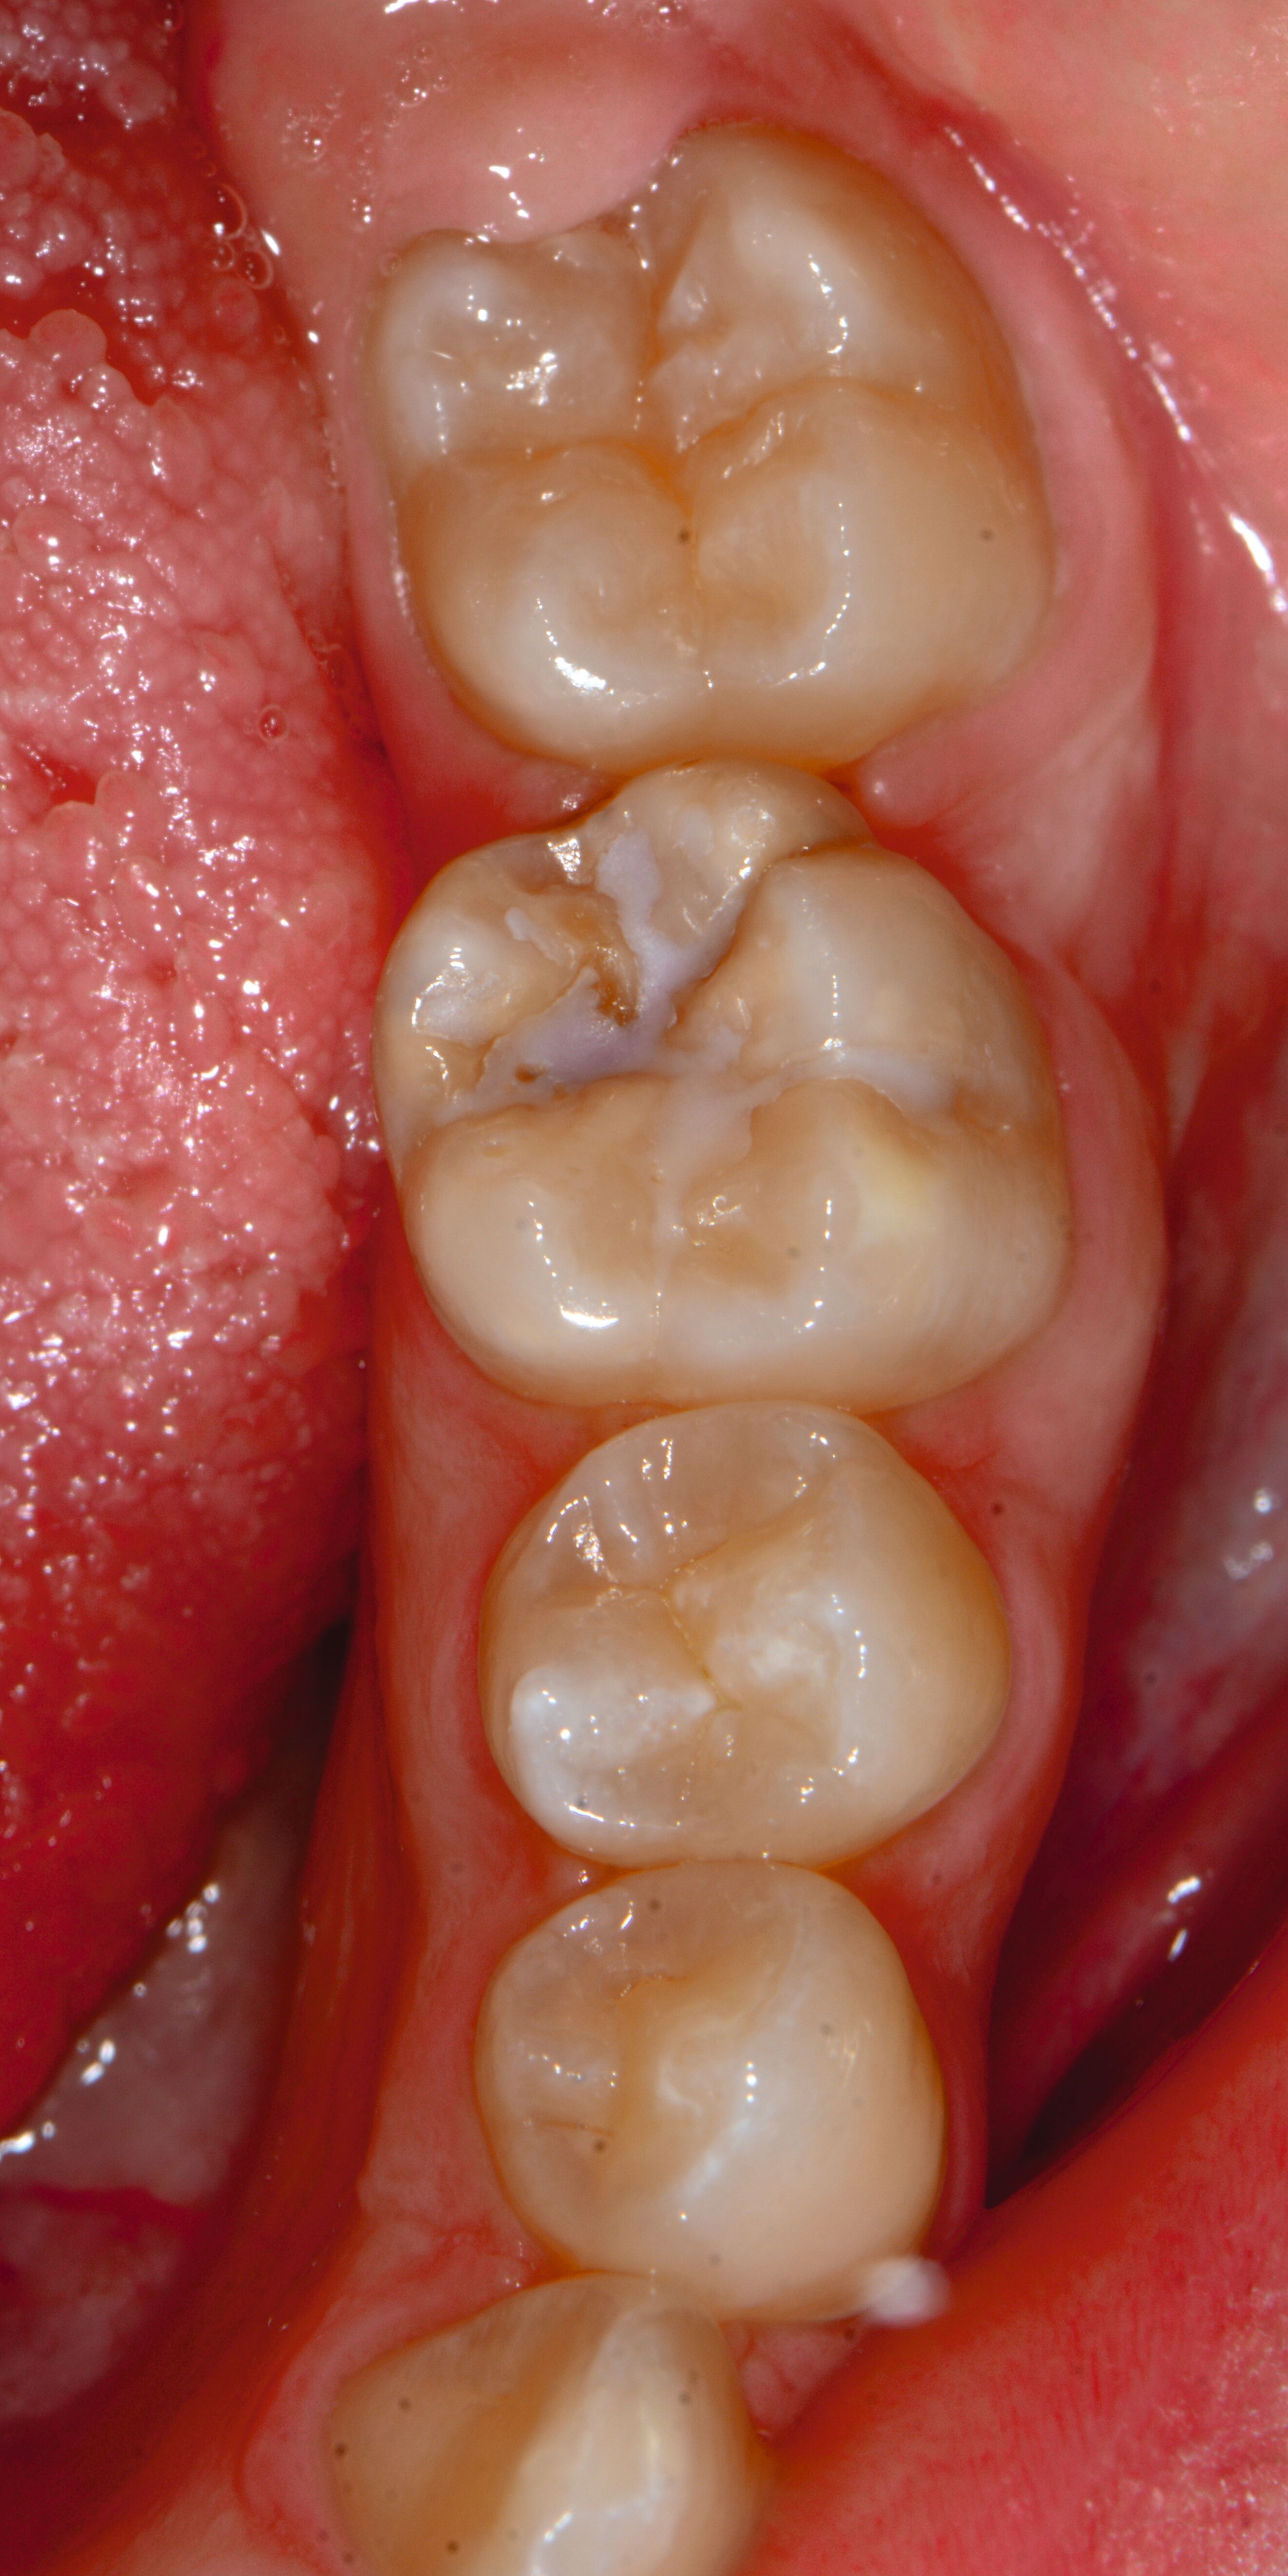

Bei post- beziehungsweise präeruptiven Oberflächendefekten ergibt sich in einigen Fällen die Indikation zur Restauration dieser MIH-Zähne. Unter Verweis auf die Lokalisation von MIH-bedingten Hypomineralisationen außerhalb der typischen Kariesprädilektionsstellen – zum Beispiel okklusale Fissuren und Grübchen oder Approximalflächen – werden diese als „atypische Restaurationen“ (engl.: „atypical restoration“, Abbildung 6) klassifiziert. Als ein weiteres Erkennungsmerkmal gilt die Präsenz von Hypomineralisationen im Bereich der Restaurationsränder. MIH- und kariesbedingte Restaurationen können und sollten sicher voneinander abgegrenzt werden.

Für die Dokumentation und Klassifikation der MIH wurden verschiedene Systeme vorgeschlagen. Als historisch und veraltet gilt der (modifizierte) DDE-Index. Demgegenüber haben die Kriterien der EAPD – abgegrenzte Opazitäten (Abbildung 3 und 4), Schmelzeinbrüche (Abbildung 5), atypische Restaurationen (Abbildung 6) – mittlerweile die weiteste Verbreitung gefunden. Diese wurden 2003 erstmals zur Beschreibung der MIH auf empirischer Basis publiziert [Weerheijm et al., 2003] und den Jahren 2010 und 2022 im Rahmen der damaligen MIH-Workshops bestätigt [Lygidakis et al., 2010; 2022].